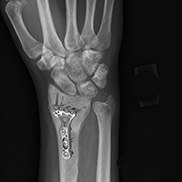

Wrist Fracture Fixation

Wrist fracture fixation may be performed by surgical or non-surgical methods depending on the severity of the fracture...Read More

Wrist Open Reduction and Internal Fixation

Open reduction and internal fixation of the wrist is a surgical technique employed for the treatment of severe wrist fractures to restore... Read More